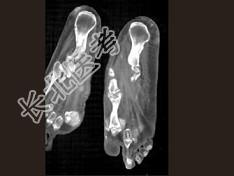

- 单项选择题男,55岁, 趾骨疼痛,皮肤红肿, 可触及结节,实验室检查高血尿酸, 结合图像,最可能的诊断是 ( )

C、痛风